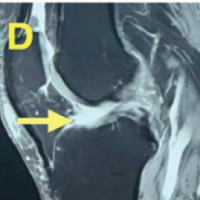

Moderate hemarthrosis was present in both of his knees. X-ray findings revealed patella baja with calcification in the quadriceps tendon. Magnetic resonance imaging confirmed bilateral QTR near the patellar attachment on both sides (Fig. 2).

Figure 2: Magnetic resonance imaging films showing a complete tear of the patellar attachment of the quadriceps.